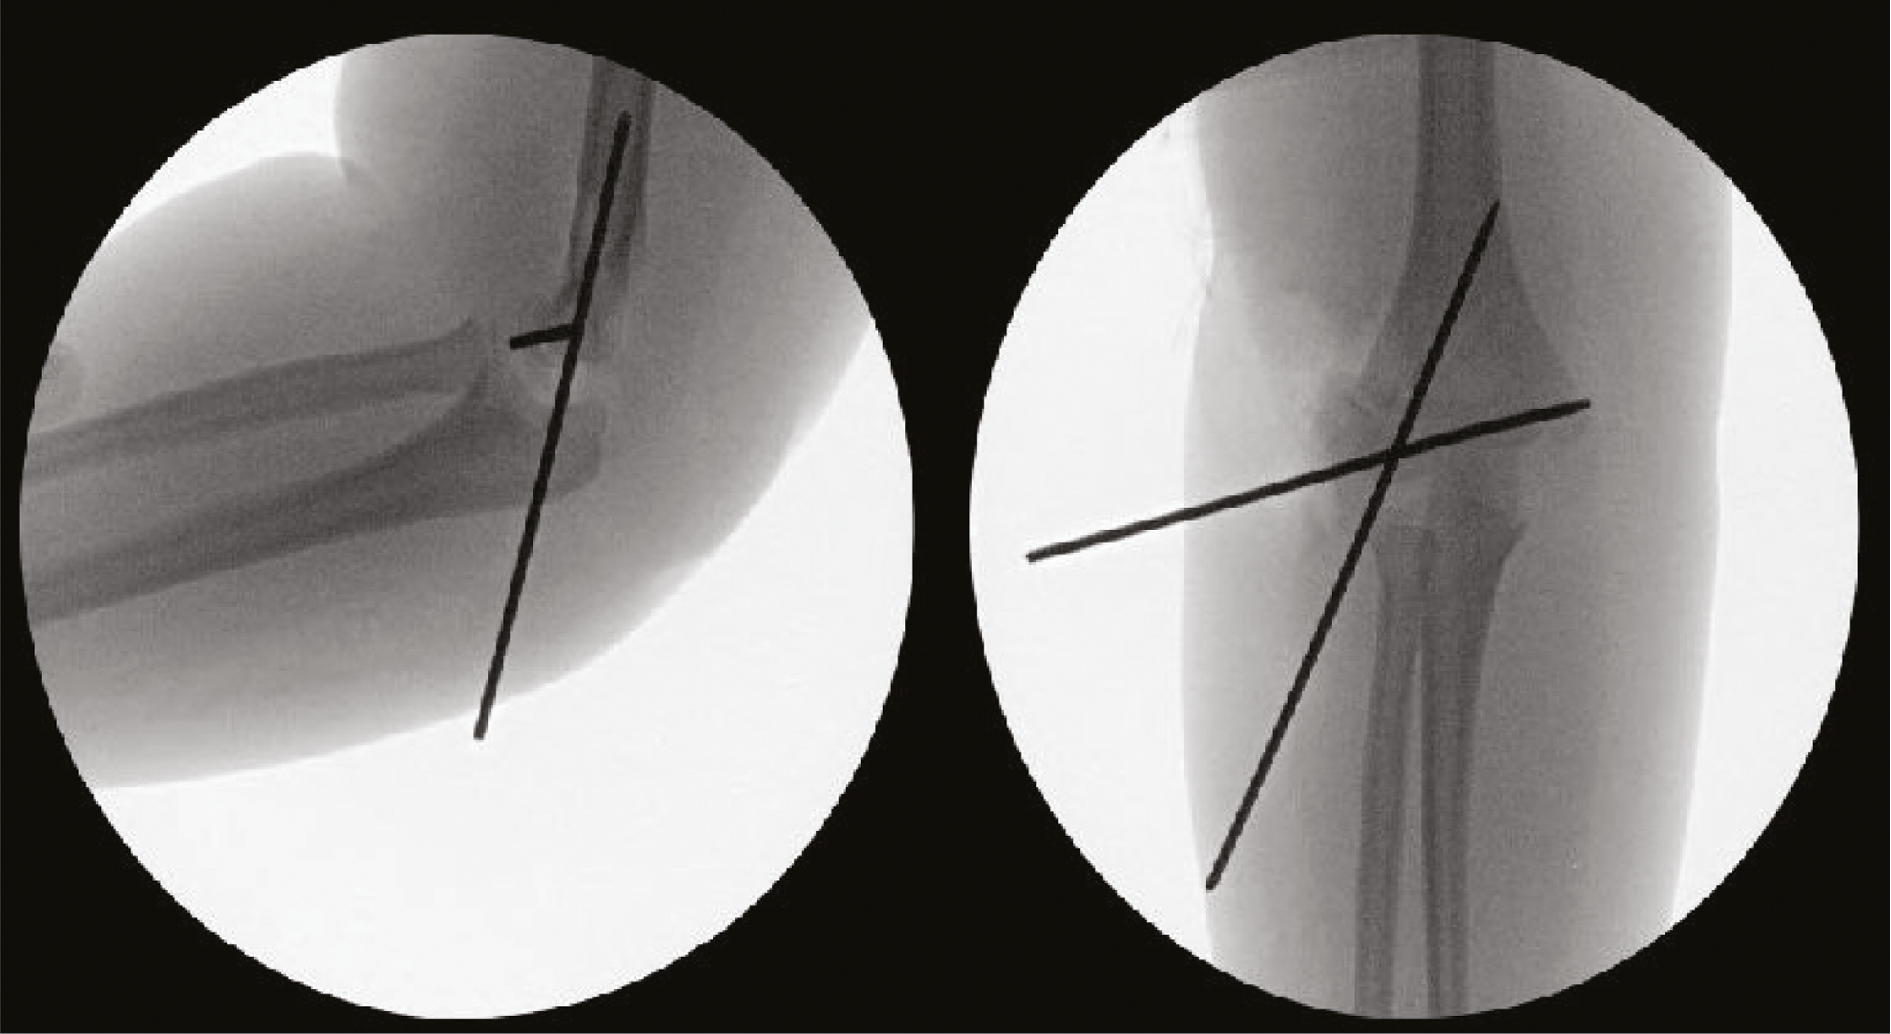

Two or three K-wires are then inserted in a divergent fashion across the fracture site. Utilizing a two-pin construct, one pin should serve as the articular pin aiming for the medial epicondyle in a lateral to medial direction. The second pin should be directed up the lateral column with a goal divergence angle of at least 60 degrees if possible5 (Figure 14).

Figure 14. AP and lateral fluoroscopic images showing reduced and pinned lateral condyle fracture. Notice the ideal positioning of the two-pin configuration.

Success in this technically challenging procedure is best achieved with the use of an assistant—one surgeon holds reduction while another places the pins. Through direct visualization (Figure 15) and then palpation of the articular surface with a Freer elevator, the reduction is verified with fluoroscopic confirmation of reduction and proper pin placement. If there is concern about stability, a third pin can be placed in a divergent fashion. Good results have also been achieved utilizing a single 3.5/4.0 mm partially threaded, cannulated screw if greater stability is indicated. It should be oriented perpendicular to the fracture plane and often a second wire is placed to control rotation during drilling and screw insertion. This screw may become symptomatic in the future and necessitate elective removal.